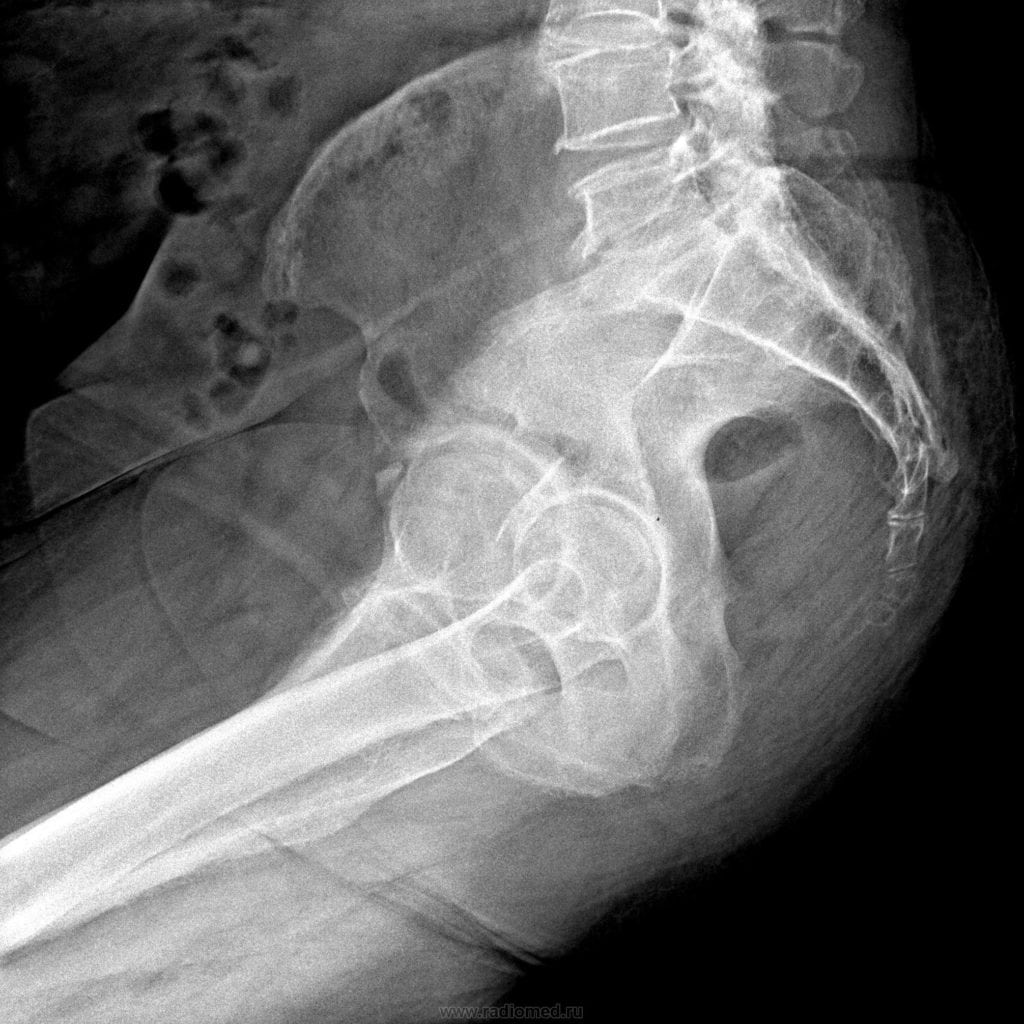

Травмы копчика

Перелом копчика происходит довольно редко, обычно во время серьезных дорожно-транспортных происшествий при ударе. В момент травмирования боль острая, пронизывающая, вызывающая помутнение сознания. На реабилитационном этапе ее интенсивность существенно снижается, но дискомфорт в нижней части спины ощущается еще несколько месяцев, особенно при ОРВИ, рецидивах хронических патологий, смене климатических поясов.

В результате падения, ушиба, длительного сдавливания боль возникает из-за травмирования соединительнотканных структур — кожи, связок, мышц сухожилий. На поврежденном участке образуется гематома, сильный отек. При надавливании на него болезненность усиливается, распространяется на бедра, отдает в бока.

Так как боль в копчике у мужчин может возникать по множеству причин, то требуется проведение дифференциальной диагностики. Поэтому пациенту назначается ряд инструментальных исследований: рентгенография, УЗИ, МРТ или КТ. При подозрении на инфекционное происхождение патологии проводятся биохимические, серологические лабораторные анализы. Посев биологических образцов в питательные среды позволяет установить видовую принадлежность микроорганизмов и их чувствительность к противомикробным препаратам.